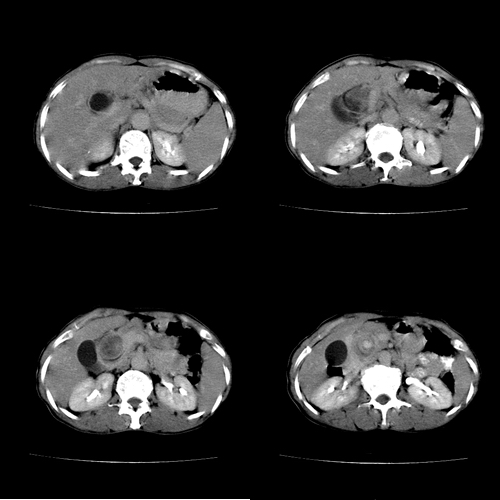

患者 女 60岁,曾多年胆结石及胆管结石,今行ct复查,非常经典.现上传,请讨论.

典型的胆总管铸型结石。

胆总管内多层同心圆样结石,确属精典,谢谢卜一老师!

同心圆样改变.典型!这样的石子值多少钱?

肝内胆管扩张形态也支持胆总管结石的表现